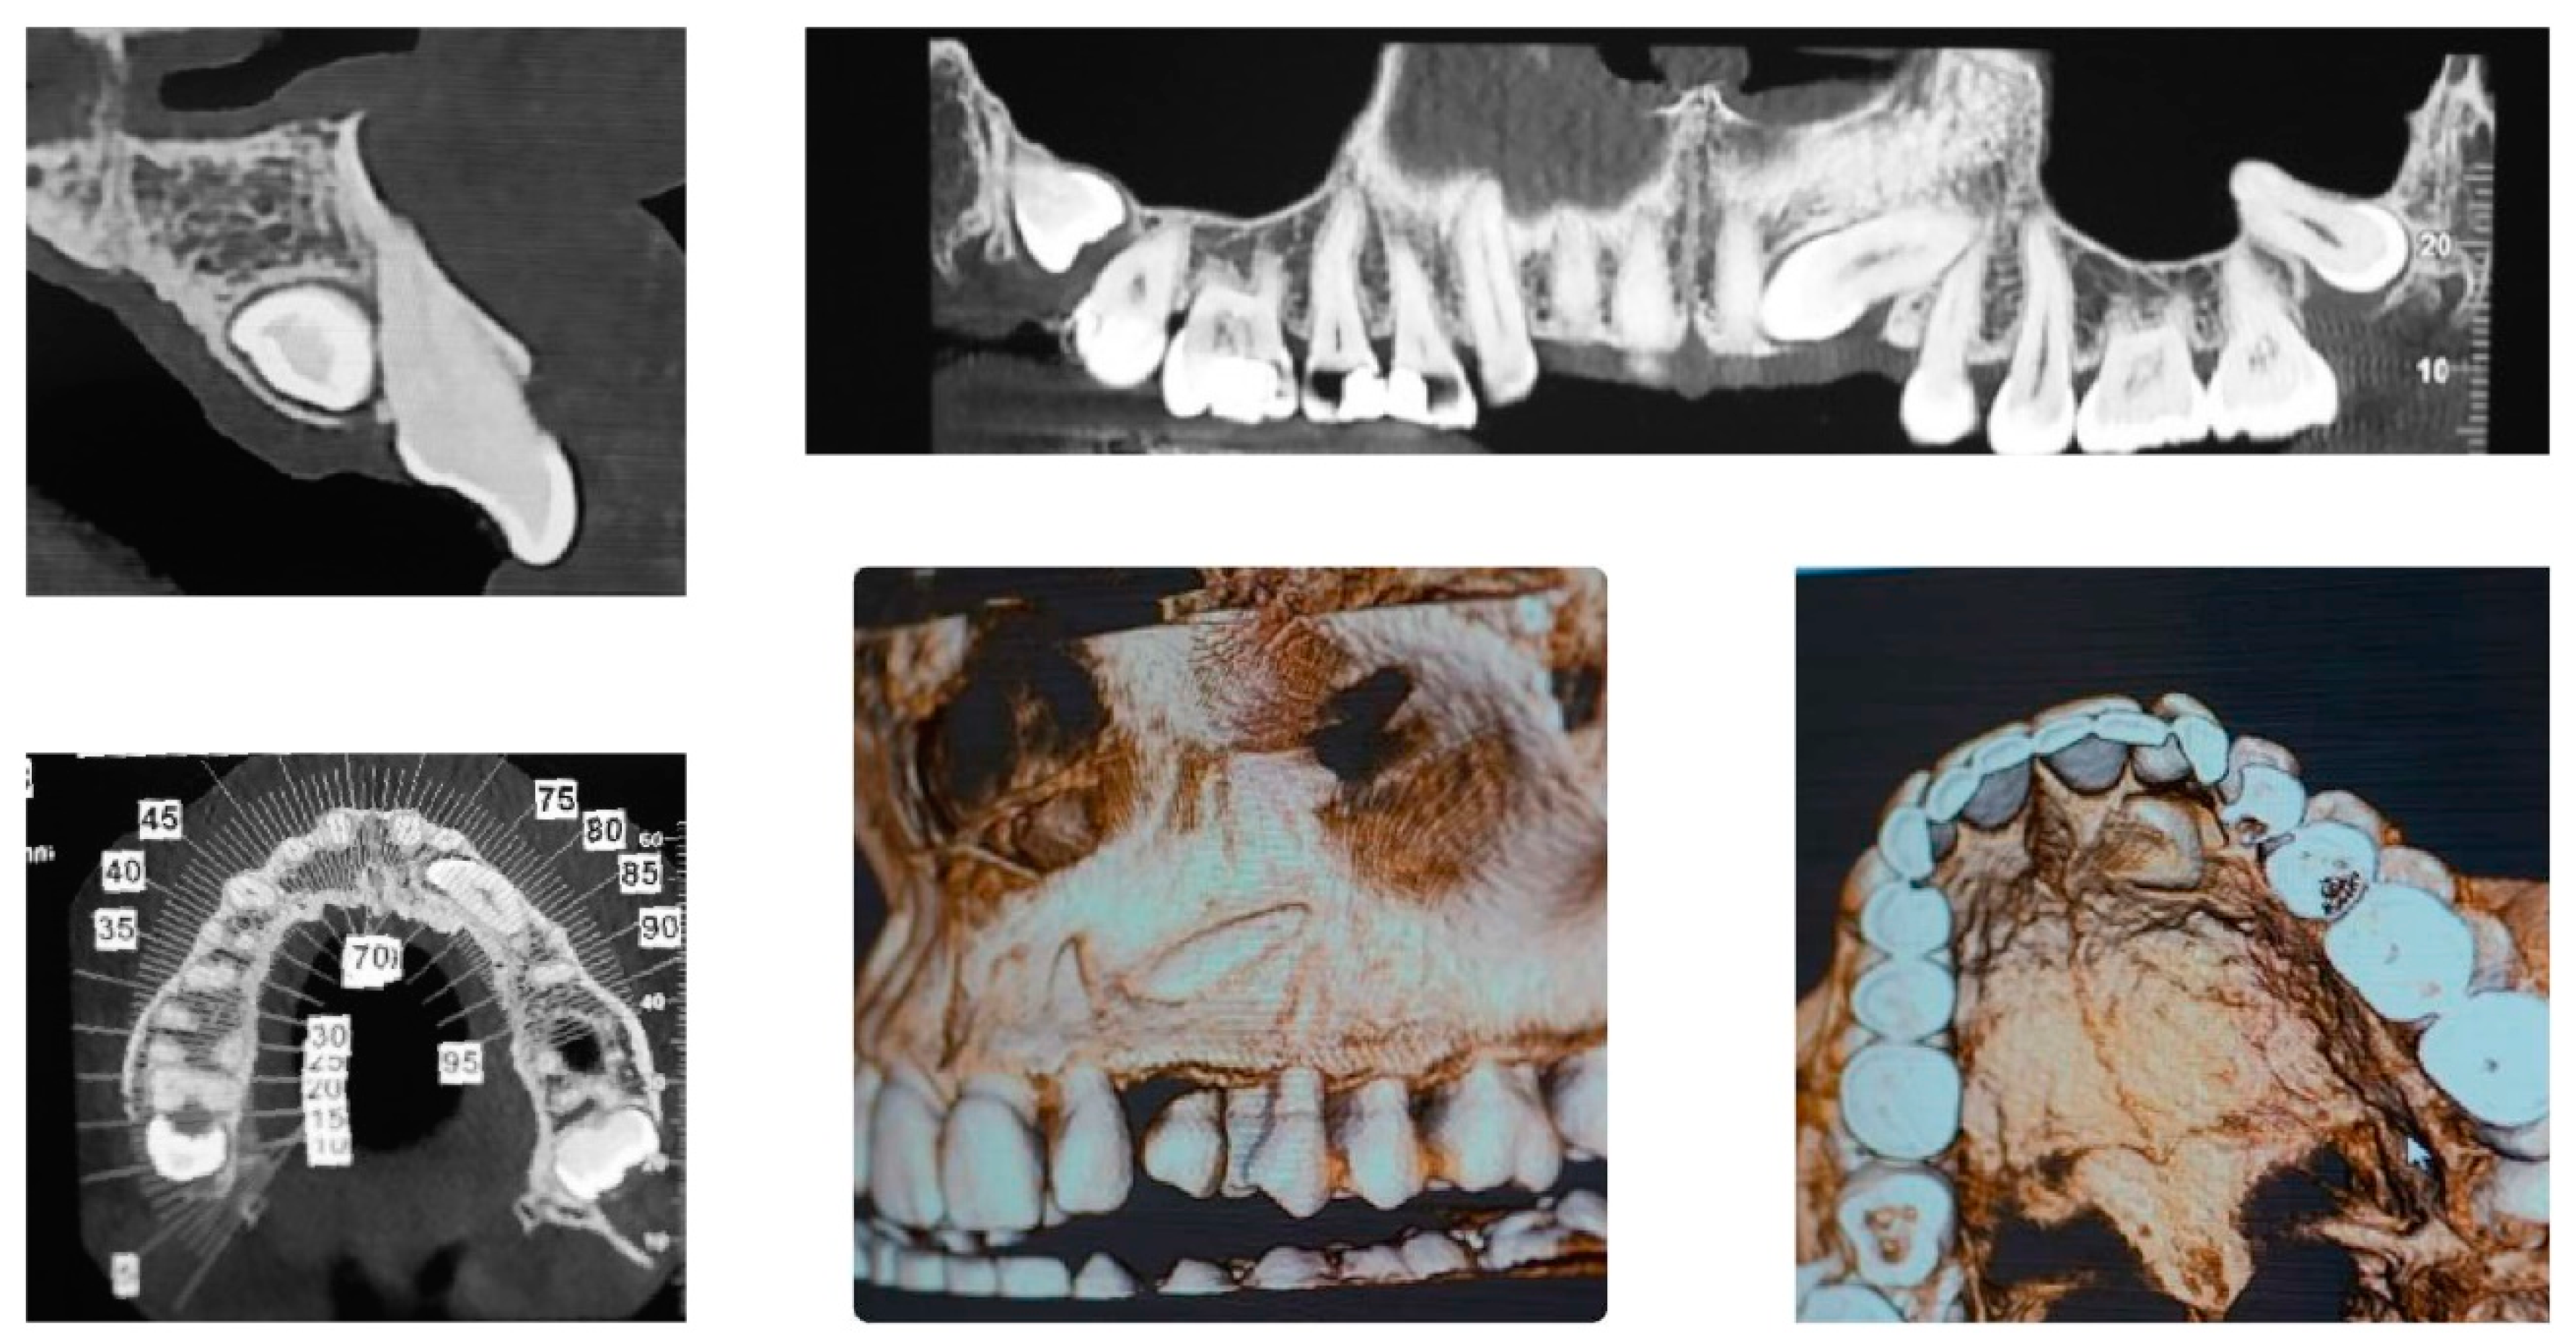

Figure 2 panoramic and CBCT showing the moderate palatal 2.3 impaction. Lateral X-rays confirming a Class I skeletal and dental malocclusion with deep bite.

Figure 2.

Cephalometric analysis, panoramic and CBCT of the first patient. Lateral X-rays confirming a Class I skeletal and dental malocclusion with deep bite.